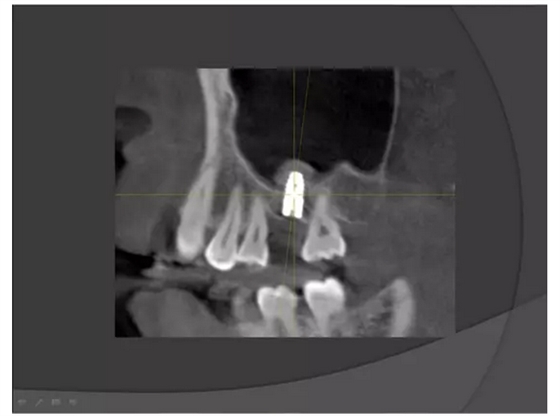

上頜竇種植手術(shù)概述